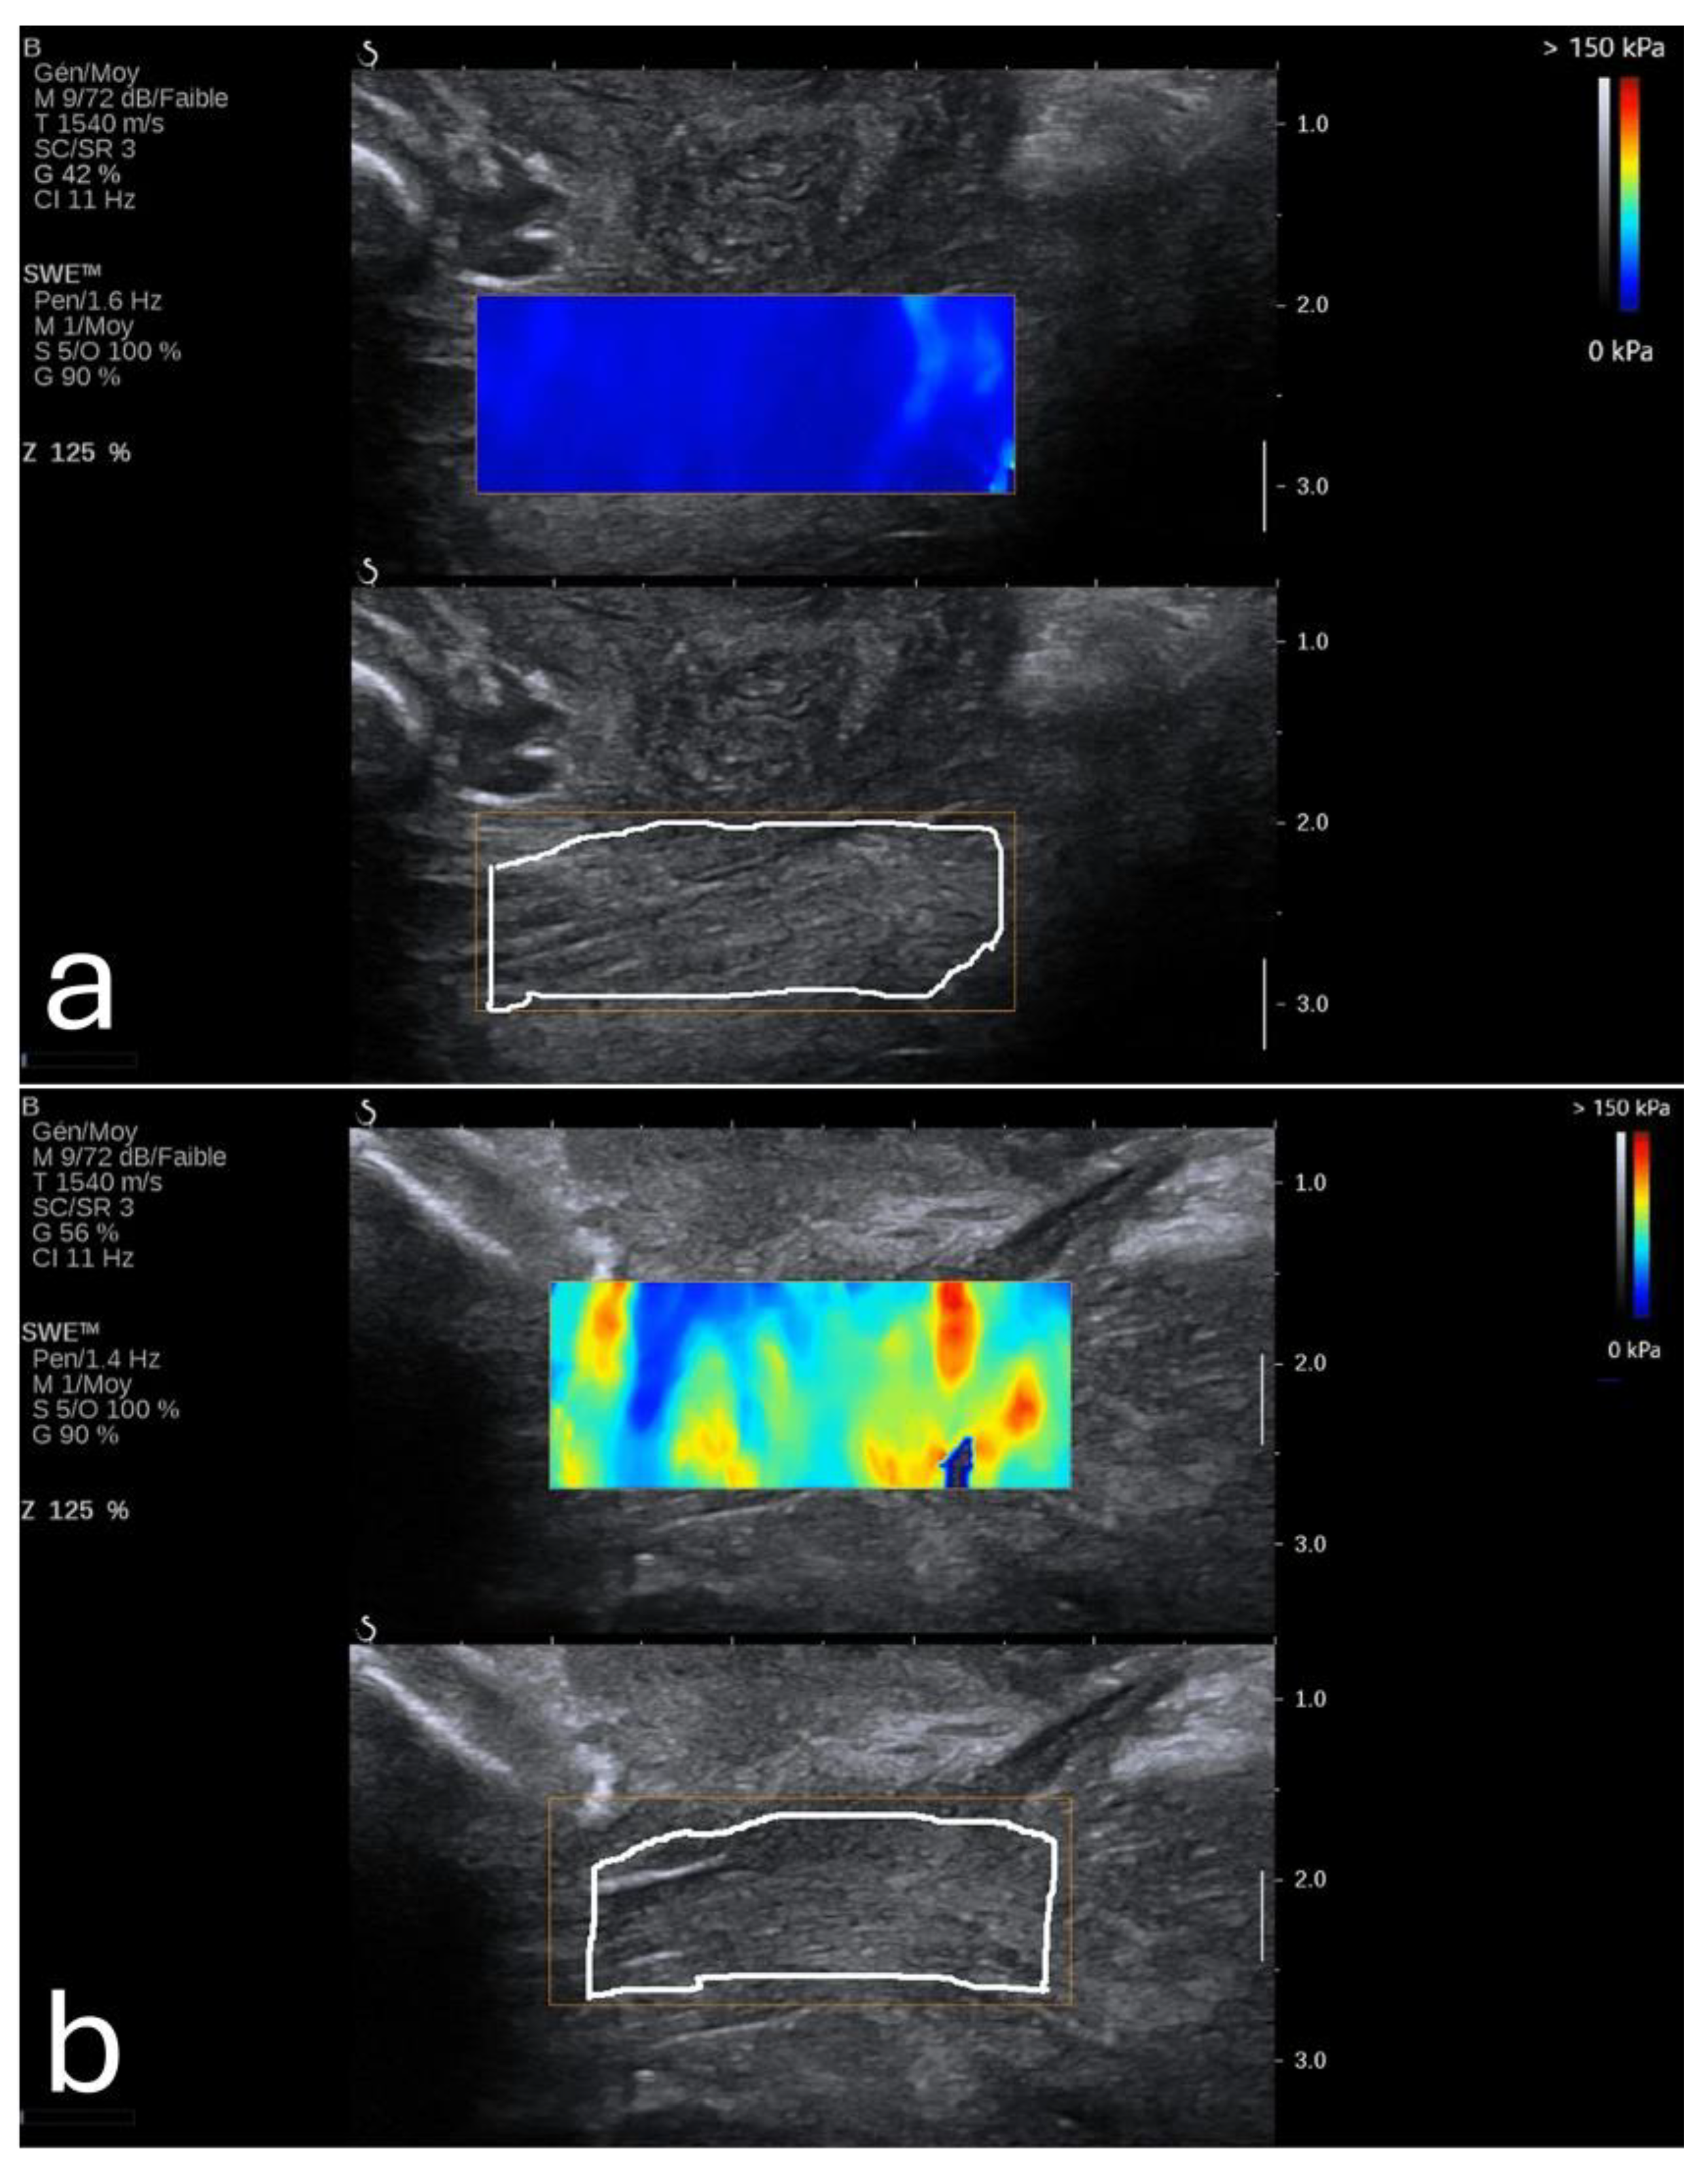

Elasticity in the PFM enables them to respond dynamically to increased abdominal pressure and other physical stresses. For instance, during actions such as the Valsalva maneuver or maximal contraction, the LAM and EAS demonstrate considerable elasticity, which provides resilience against deformation (Figure 3) [49]. This quality is particularly critical for maintaining the integrity of the pelvic organs and facilitating controlled movement.

Figure 3. Shear wave elastography of the levator ani muscle at rest (a) and during a Valsalva maneuver. Image adapted from Gachon et al. [53] under a Creative Commons Attribution 4.0 International License. Changes were made to resize and adjust the images.